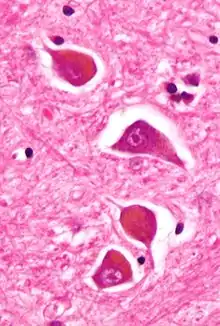

| Micrograph of Alzheimer type II astrocytes, as may be seen in hepatic encephalopathy | |

There are various explanations why liver dysfunction or portosystemic shunting might lead to encephalopathy. In healthy subjects, nitrogen-containing compounds from the intestine, generated by gut bacteria from food, are transported by the portal vein to the liver, where 80–90% are metabolised through the urea cycle and/or excreted immediately. This process is impaired in all subtypes of hepatic encephalopathy, either because the hepatocytes (liver cells) are incapable of metabolising the waste products or because portal venous blood bypasses the liver through collateral circulation or a medically constructed shunt. Nitrogenous waste products accumulate in the systemic circulation (hence the older term "portosystemic encephalopathy"). The most important waste product is ammonia (NH3). This small molecule crosses the blood–brain barrier and is absorbed and metabolised by the astrocytes, a population of cells in the brain that constitutes 30% of the cerebral cortex. Astrocytes use ammonia when synthesising glutamine from glutamate. The increased levels of glutamine lead to an increase in osmotic pressure in the astrocytes, which become swollen. There is increased activity of the inhibitory γ-aminobutyric acid (GABA) system and the energy supply to other brain cells is decreased. This can be thought of as an example of brain edema of the "cytotoxic" type.[13]